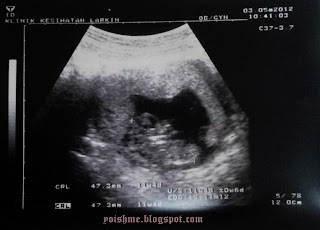

The last process is when they send me to see the doctor. The doctor asking me about my last period so, I said I forget about it. Then he decided to do the IUGS. I was so nervous. I hope I can see something in my tummy. I don’t know, maybe I am ready to be a mom. Well, the ‘Gojes’ one at least. HAHHAHA…

But then, there you are. Small ‘little bean’ stuck in my uterus. Hahahha!! Skema ya’ll. It got me into tears. I was extremely happy, but the doctor really spoil it though, he said it’s too early, too small, he can’t tell how old is my pregnancy. I just don’t care. It is officially proved that I am PREGNANT!!

So, he said, my pregnancy might be between 1 to 2 weeks old. He assigned 3rd May 2012 for me to come again to check on my pregnancy age. He gave me folic acid to be take one for every day after a meal. Fuh, what a process!! I can’t hide my feeling!! So I spread the good news to all my others heartbeats and friends to share my happiness. Uit…what about my hubby? He can barely stand!!! Hahahhahahah!!! He was in surprise. We were in surprise, but he never expected to be a father this soon! Hahhaha!! So, honey, we gonna have a very cute little eyes baby soon this year. Work harder than before!! Hahhahahha!!!